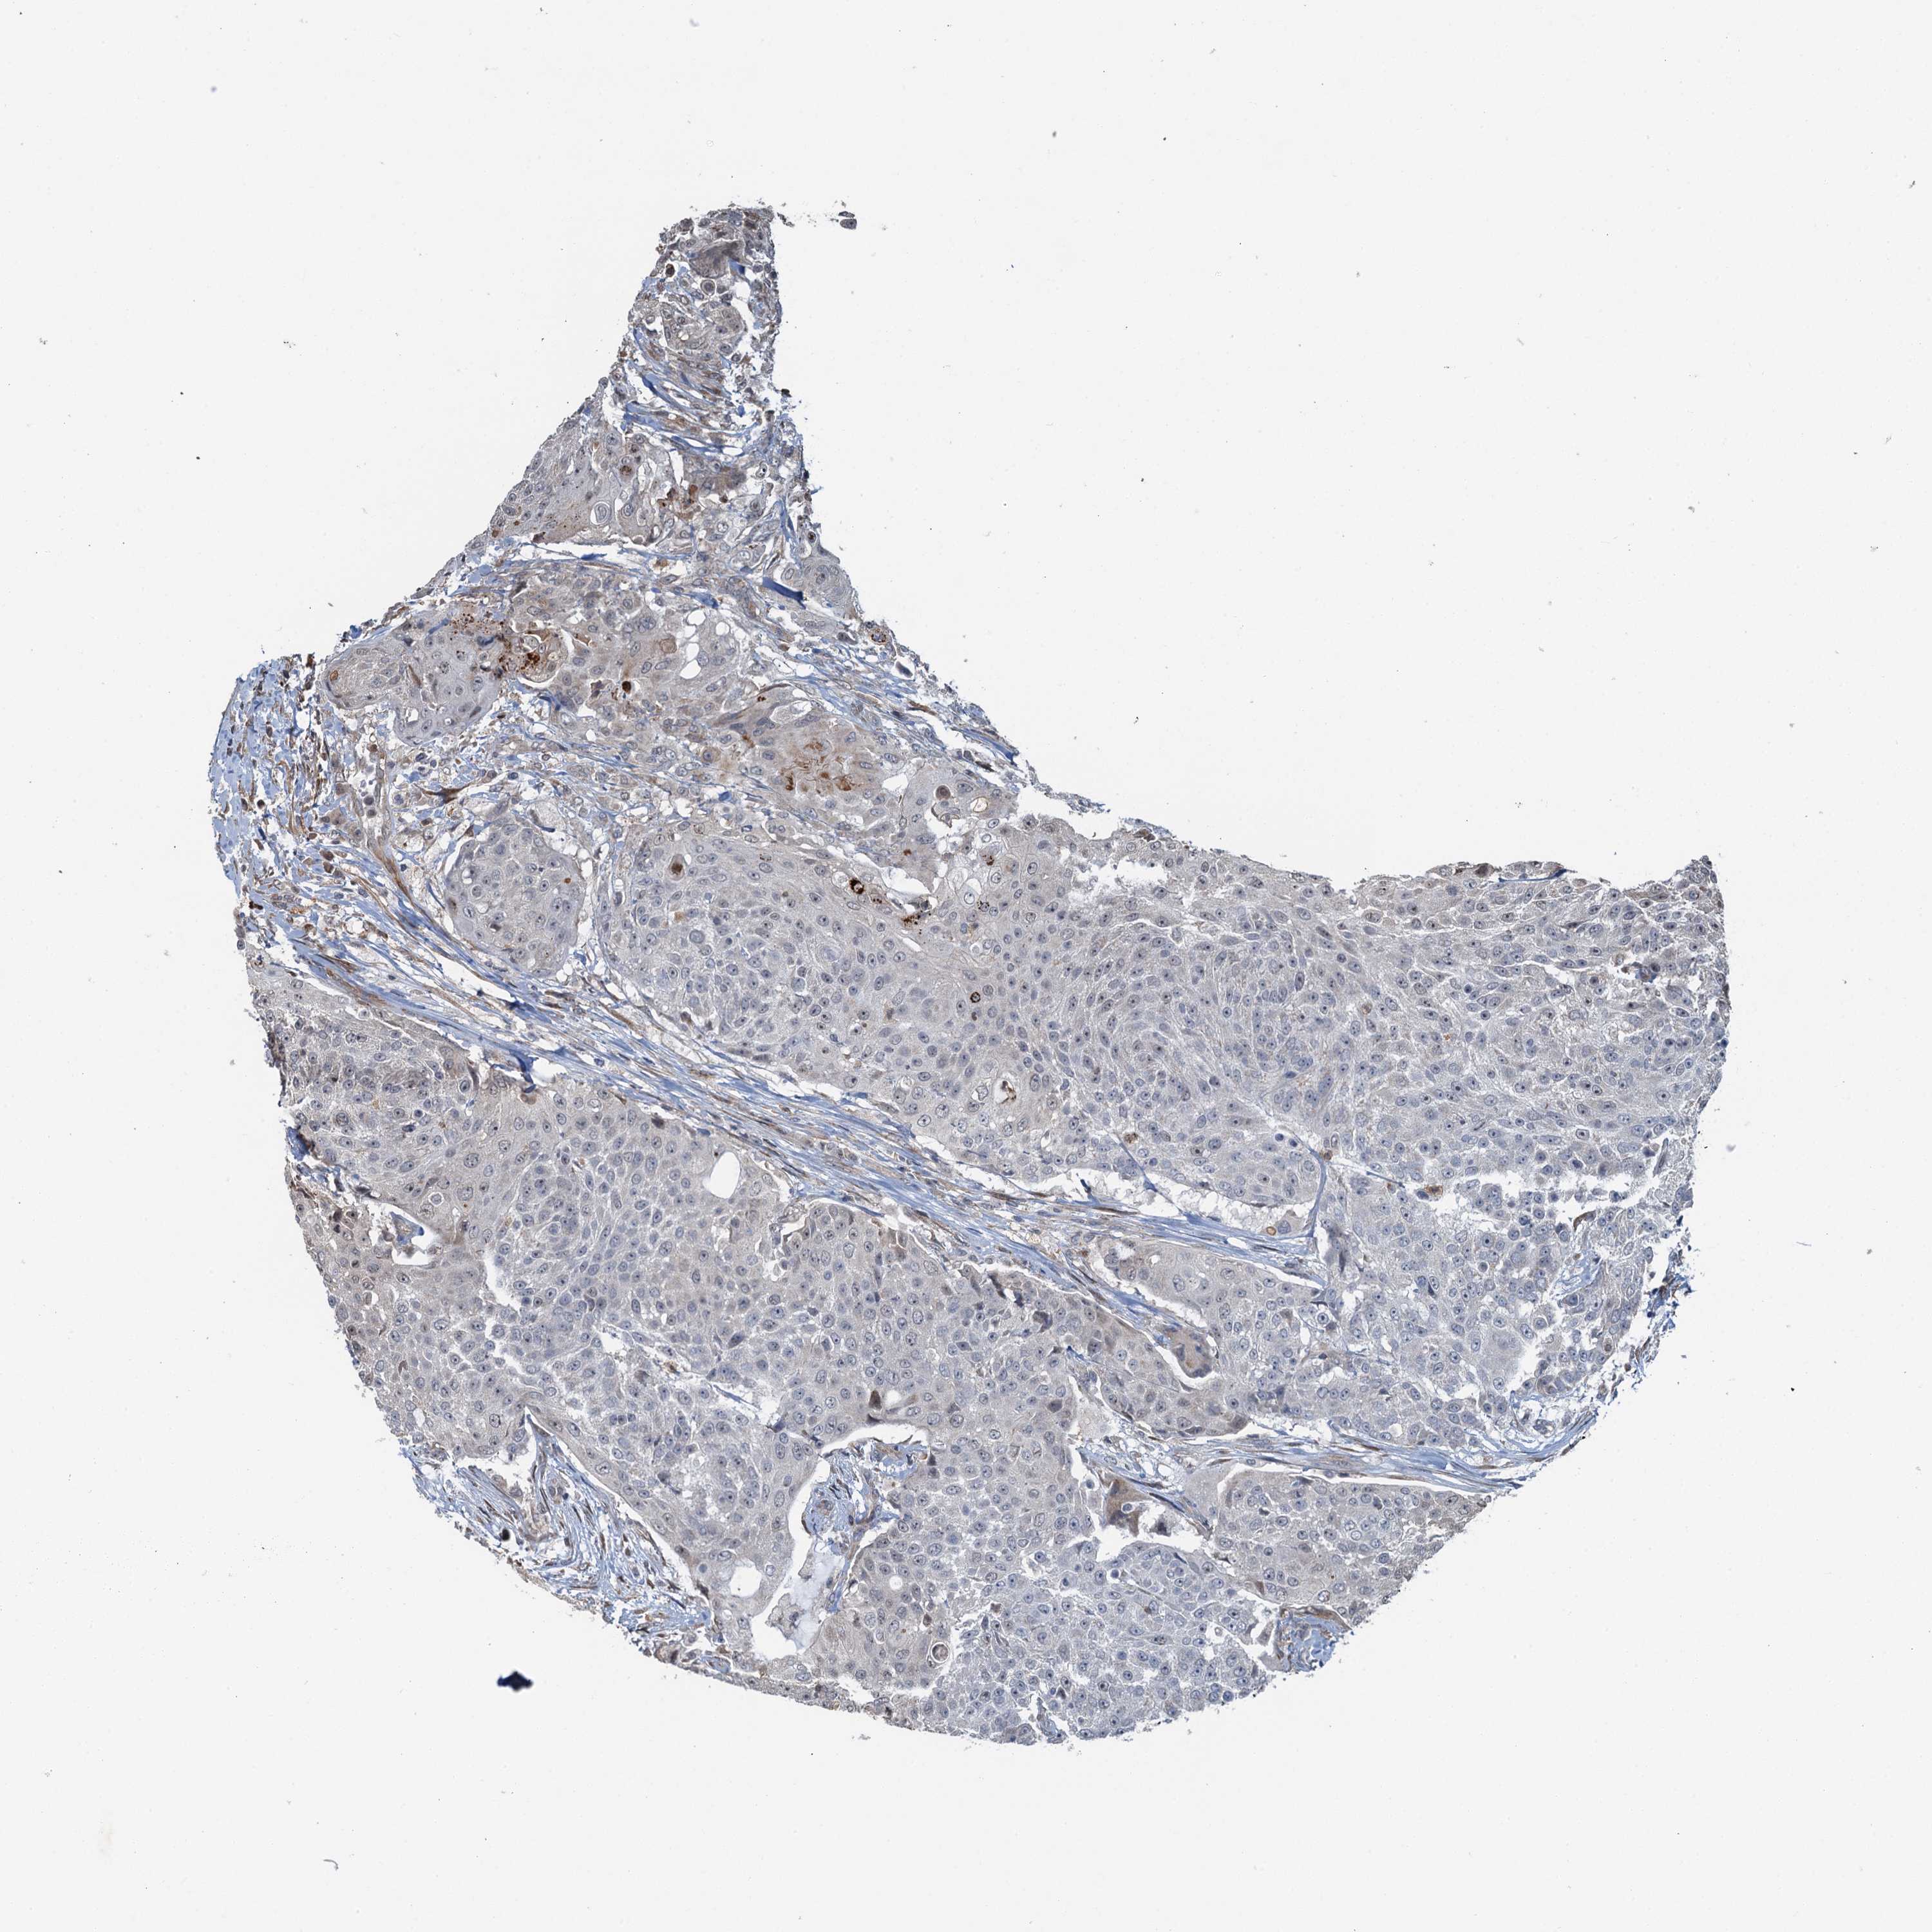

UROTHELIAL CANCER - Protein expressioni

A mouse-over function shows sample information and annotation data. Click on an image to view it in a full screen mode. Samples can be filtered based on level of antibody staining by selecting one or several of the following categories: high, medium, low and not detected. The assay and annotation is described here.

Note that samples used for immunohistochemistry by the Human Protein Atlas do not correspond to samples in the TCGA dataset.

Antibody stainingi

Antibody staining in the annotated cell types in the current human tissue is reported as not detected, low, medium, or high, based on conventional immunohistochemistry profiling in selected tissues. This score is based on the combination of the staining intensity and fraction of stained cells.

Each image is clickable and will lead to virtual microscopy that enables deeper exploration of all samples and also displays staining intensity scores, fraction scores and subcellular localization as well as patient and tissue information for each sample.

Antibody HPA039690

Antibody HPA040231

Urothelial carcinoma, High grade

Urothelial carcinoma, Low grade